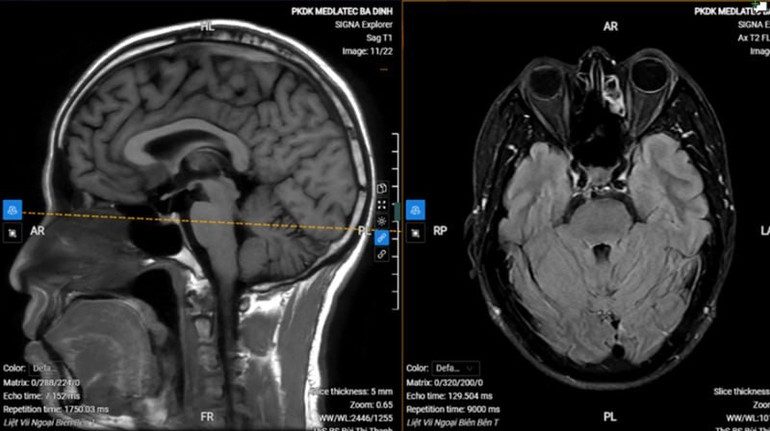

Chụp MRI sọ não cho thấy hình ảnh thoái hóa myelin chất trắng dưới vỏ bán cầu đại não bên hai bên (phân loại Fazekas độ 1), không thấy tổn thương cấp tính nội sọ.

Với kết quả trên, anh S. được chẩn đoán liệt dây thần kinh số VII ngoại biên trái vô căn (liệt Bell). Bệnh nhân được kê đơn điều trị ngoại trú, hướng dẫn tập các bài tập cơ vùng mặt, chăm sóc mắt, phối hợp châm cứu sau 1 tuần.

Hình ảnh chụp MRI của bệnh nhân.